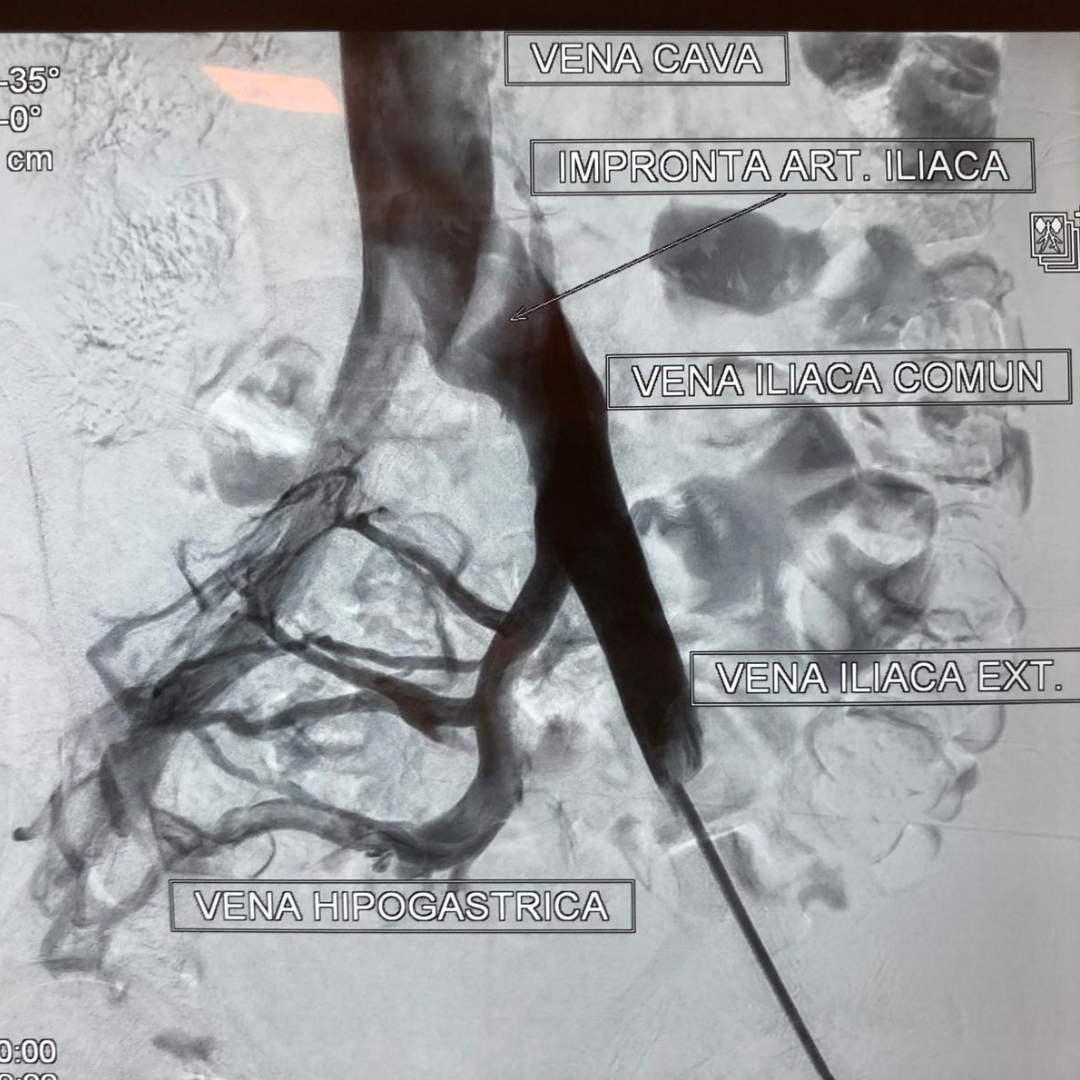

Pre-treatment: Bilateral iliac vein occlusion

Pre-treatment

Bilateral iliac vein occlusion associated with pelvic congestion syndrome.

• Deep Venous Reconstruction (Iliofemoral and Post-Thrombotic Disease) Specialized management of iliofemoral obstruction, post-thrombotic disease, and complex venous outflow compromise, with the goal of restoring venous return and improving functional outcomes. Guided by reconstruction of venous outflow and optimization of global hemodynamics based on individual flow patterns.